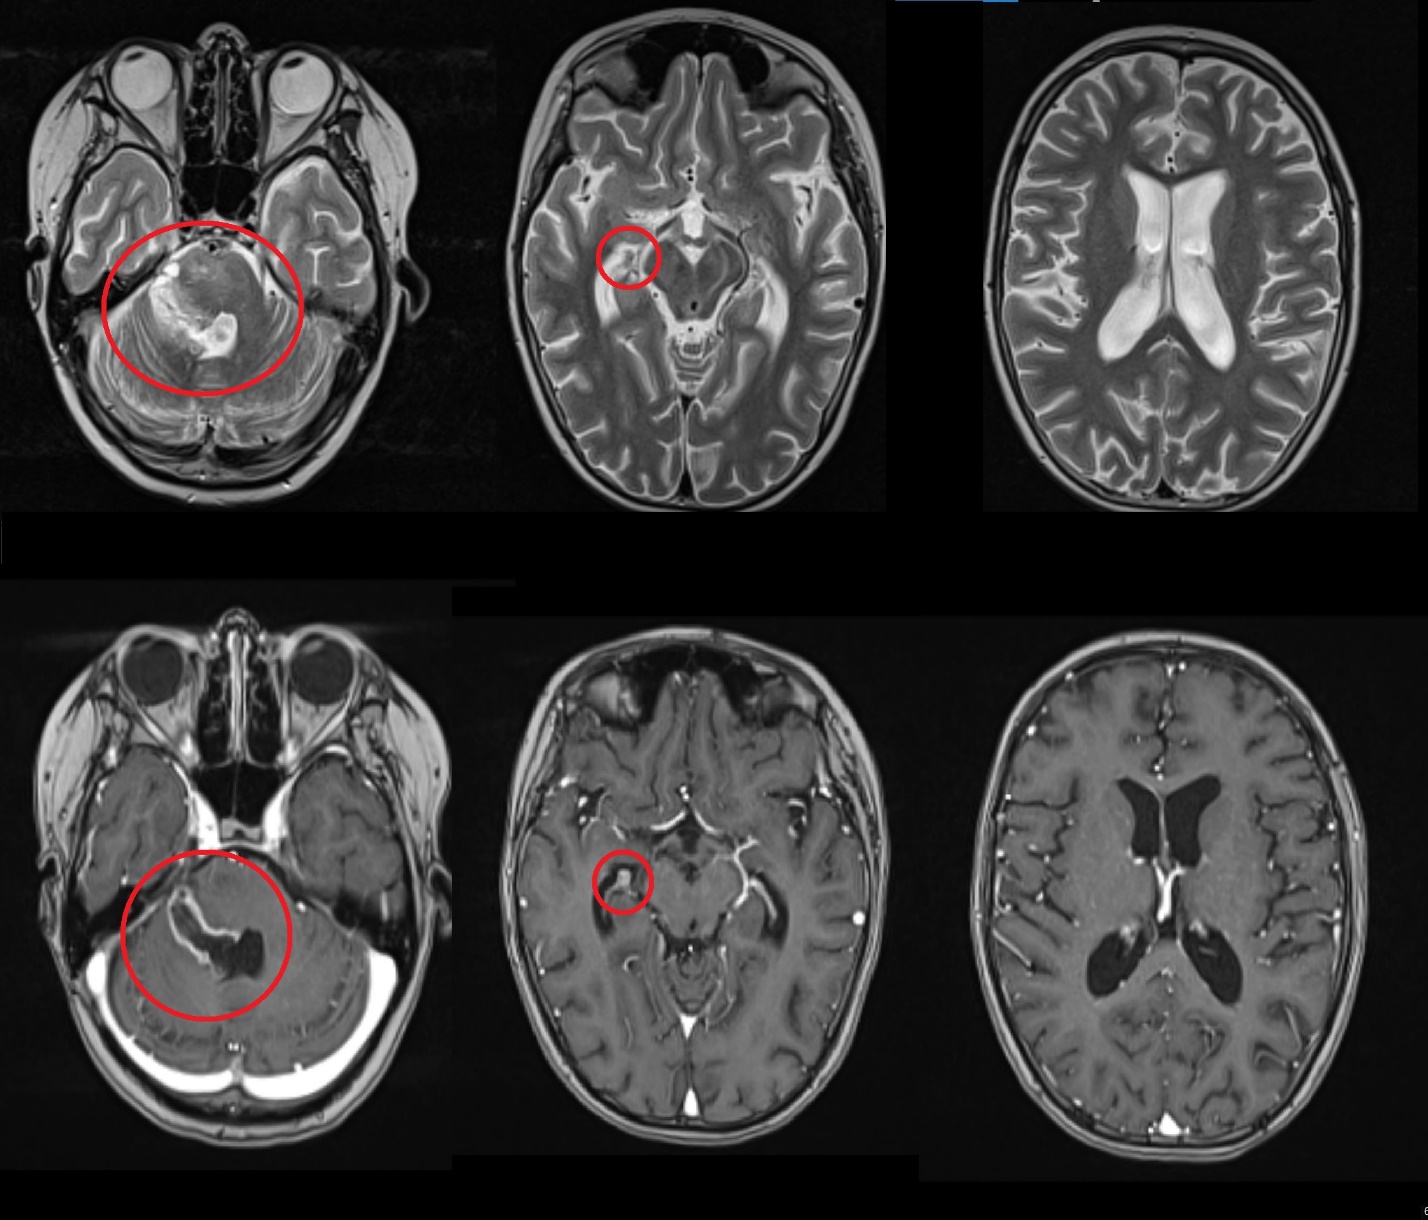

Результаты. У 19 пациентов (50 % от 38 прошедших биопсию) по данным иммуногистохимического анализа послеоперационного материала была выявлена мутация К27М в гене H3F3A. У 6 (15 %) пациентов из 38 МРТ в сроки от 2 до 5 мес (медиана – 4,5 мес) после окончания лучевой терапии выявлено нехарактерное прогрессирование ДСГ в виде метастазирования по желудочковой системе головного мозга. У остальных пациентов когорты исследования, не проходивших процедуру биопсии, подобный характер прогрессирования не наблюдался (p<0,002): у них, как правило, отмечался продолженный рост опухоли (n=96), у 4 больных диагностировано лептоменингеальное метастазирование по спинному мозгу.

Заключение. Нами выявлены случаи нетипичного прогрессирования ДСГ в виде метастазирования по желудочковой системе у детей после открытой биопсии опухоли. Есть основания полагать, что биопсия могла способствовать диссеминации ДСГ по ликворным пространствам. Необходим поиск альтернативных методов оценки молекулярно-генетических характеристик ДСГ.